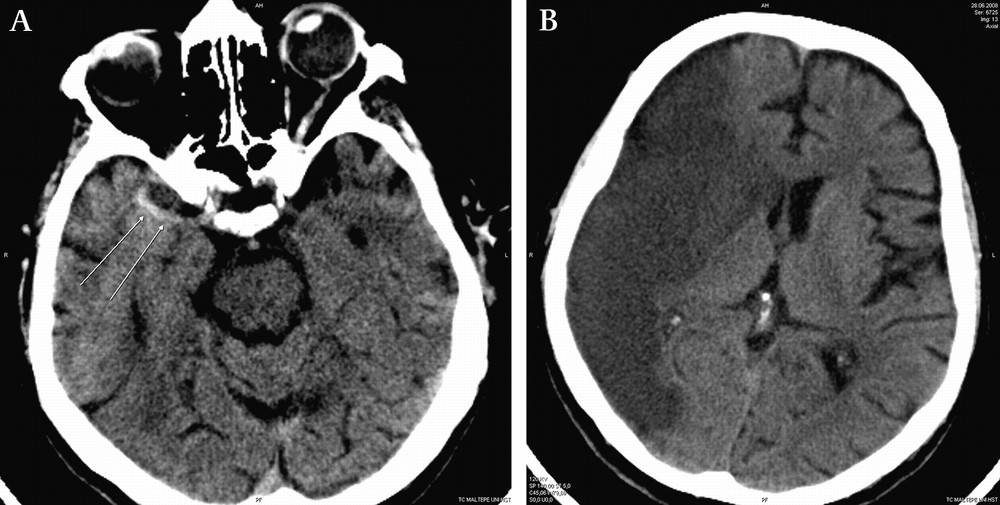

뇌출혈은 뇌 혈관이 파열되어서 발생하는 출혈을 의미합니다. 외상이나 심혈관 질환 등이 원인이 될 수 있습니다. 뇌출혈은 일반적으로 심각한 상태이며, 즉각적인 응급 조치가 필요합니다.